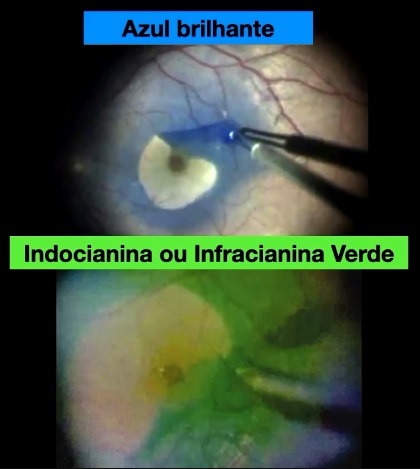

Qual corante utilizamos para corar a Membrana Limitante Interna (MLI)?

Azul Brilhante

Indocianina Verde ou Infracianina Verda